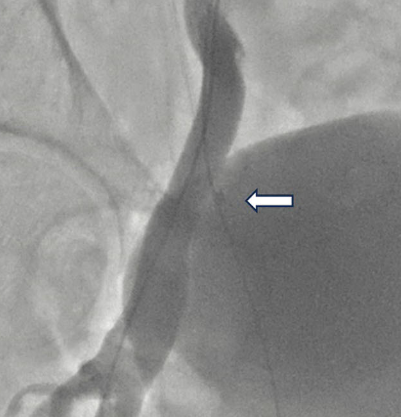

🫀 First-in-human valve-in-valve TAVI in mechanical prostheses Bench-to-bedside study: disc dislodgement & retrieval followed by successful TAVI. Published in European Heart Journal. 👉 academic.oup.com/eurheartj/adva… @escardio @PCRonline @secardiologia @CNIC_CARDIO @sacyl @TCTMD